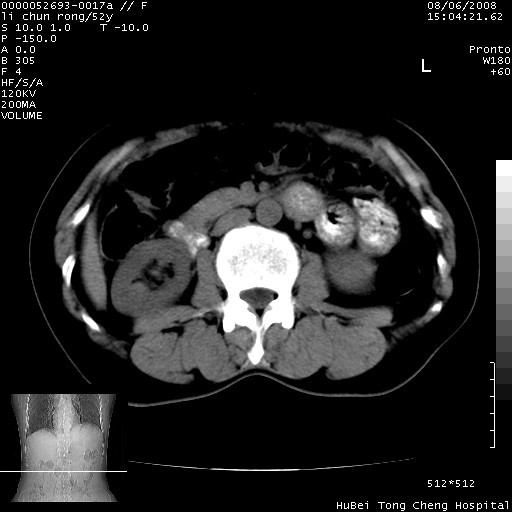

以下是引用云翔在2008-8-7 6:20:00的发言:[br]胰尾部囊性病变,考虑假囊肿,结合实验室检查疾病史

以下是引用zjzjr在2008-8-7 8:38:00的发言:[br]支持胰腺炎伴假囊肿形成,左肾小囊肿.少量腹水.

以下是引用随光逐影在2008-8-7 9:12:00的发言:[br]1)考虑胰腺炎伴假性囊肿形成可能性大;胰腺囊腺瘤待排。2)左肾小囊肿。3)少量腹水。